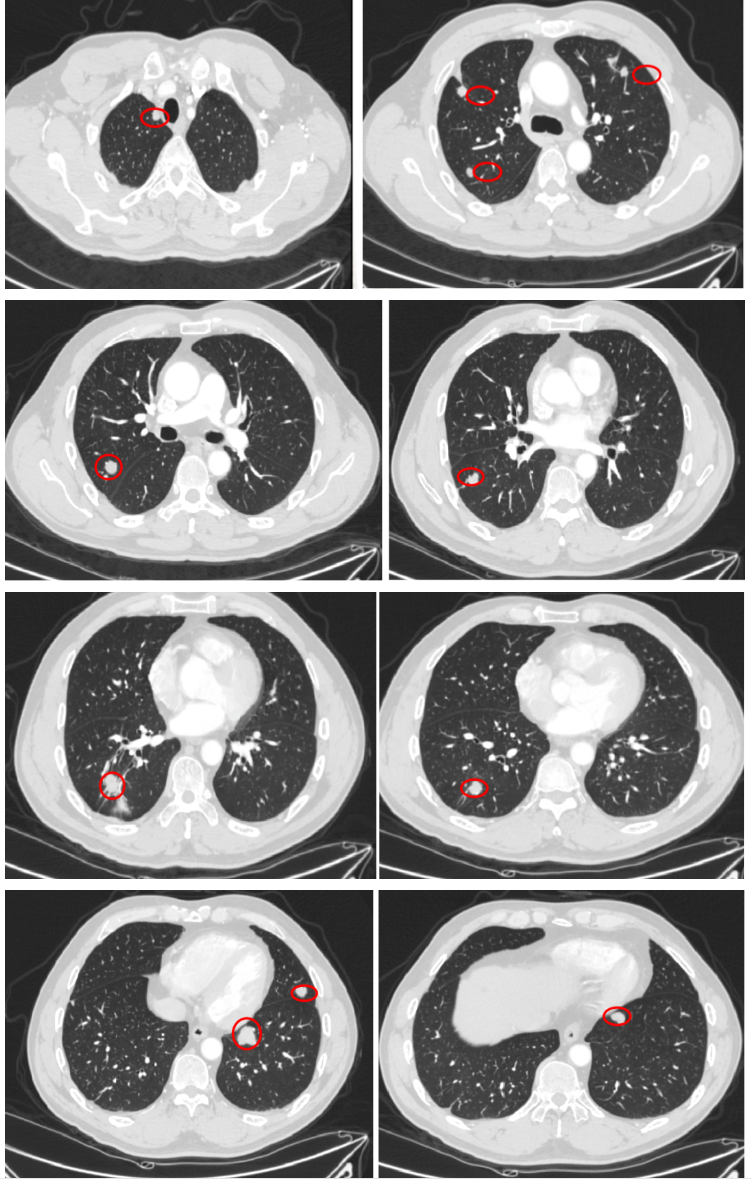

2018-10-11 胸部CT:双肺转移瘤较前进展。

2019-4至2019-6 外院行肺内转移瘤(6处)射频消融治疗。

入院诊断:直肠(上段)中分化腺癌;cT0N0M1,IV期;双肺转移;MSS型,RAS/BRAF基因野生型;ERBB2基因扩增型。